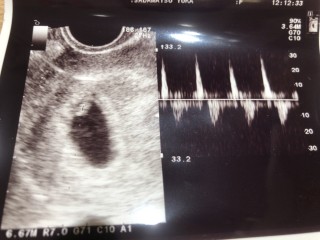

胎嚢が19.3

胎芽が2.3 …たしか(笑)

心拍確認まで出来ました(о´∀`о)

先生より詳しく説明してもらい、心音まで聴かせてくれました(´∀`)

出産予定日も決まり、早々と母子手帳の申請書を出してくれました。

次回は2週間後です♪